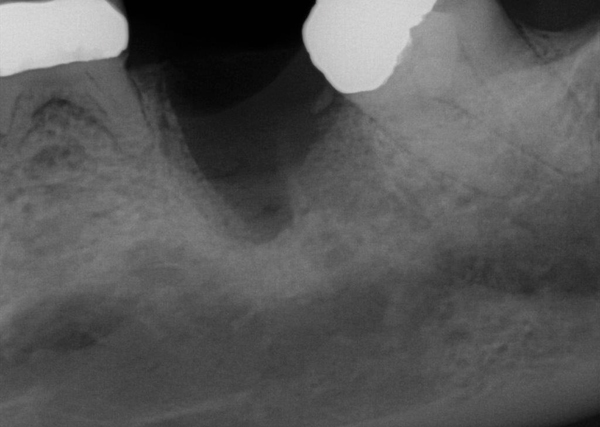

Fig 20. (Case 4) Radiograph of tooth No. 30, which had a hopeless prognosis.

Figure 20

Fig 21. Radiograph of extraction socket. Buccal plate was two-thirds resorbed.

Figure 21

Fig 22. Bone graft was placed in the socket and a d-PTFE barrier was used to cover the graft. The bone graft material was placed beyond the alveolar housing to accommodate shrinkage of graft material and to facilitate attaining a wide alveolar ridge. The barrier was removed after 5 weeks.

Figure 22